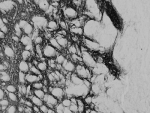

IHC staining of PFA-perfused cryosection of human hypothalamus with Proenkephalin antibody at 0.3ug/ml. HIER: pH6 citrate buffer at 80oC for 30min, Cy3-staining.